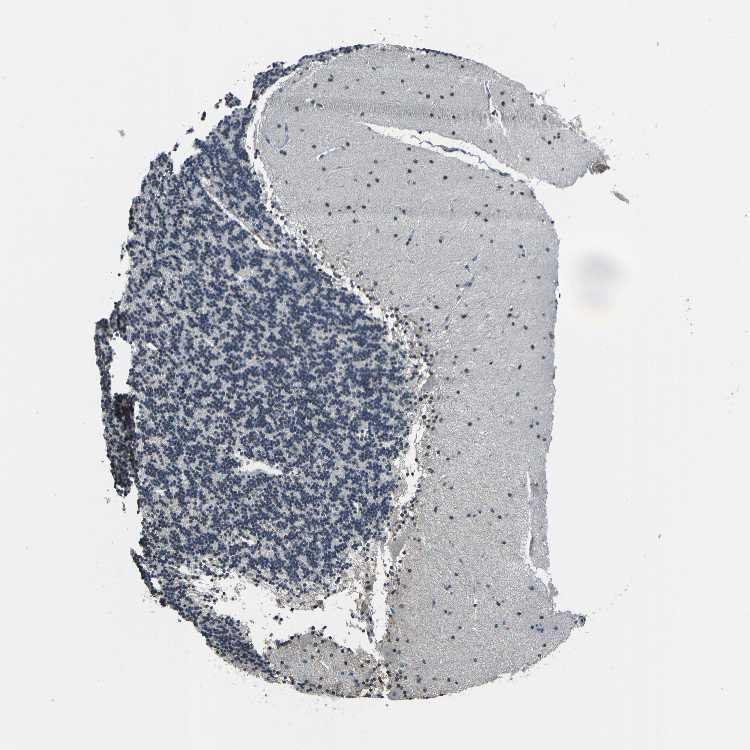

BRAIN CEREBELLUM Show tissue menu

CEREBELLUM - Expression summary

CEREBELLUM - Antibody stainingi

Antibody staining in the annotated cell types in the current human tissue is reported as not detected, low, medium, or high, based on conventional immunohistochemistry profiling in selected tissues. This score is based on the combination of the staining intensity and fraction of stained cells.

Each image is clickable and will lead to virtual microscopy that enables deeper exploration of all samples and also displays staining intensity scores, fraction scores and subcellular localization as well as patient and tissue information for each sample.

Antibody HPA017880Antibody HPA027551

Purkinje cells HighLow

Cells in granular layer Not detectedNot detected

Cells in molecular layer Not detectedLow